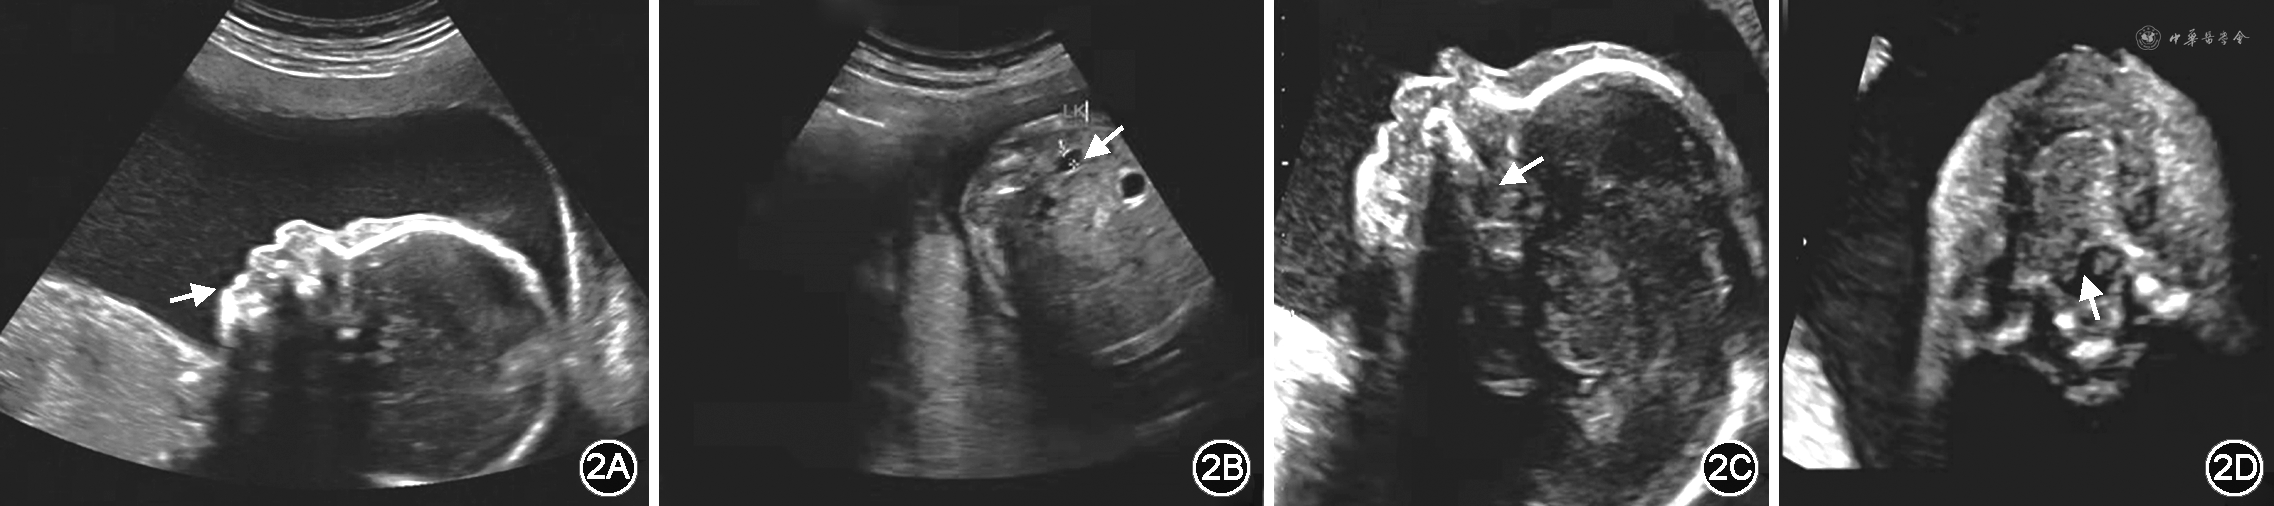

孕妇31岁,2020年5月因“停经18周+3,不良生育史”就诊于福建省妇幼保健院遗传门诊,要求产前诊断。孕妇为孕2产1,身高143 cm,面部轻度畸形(前额宽、短鼻、鼻孔前倾、人中长、上唇薄、高腭弓,图1);自幼耳道流脓,3岁因“双耳传导性听力障碍”配戴助听器,右手小指2个指节,否认近亲婚配。其配偶体健,无不良嗜好,否认腭裂家族史,否认病毒感染及致畸药物、毒物接触史。该孕妇的父亲身高172 cm,母亲身高144 cm,具有与该孕妇相似的异常面部特征。但孕妇的2个姐姐身高均为160 cm,智力、表型均正常,生育的子女亦正常。本例孕妇第1次妊娠为男孩,2019年足月经阴道分娩,生后1、5和10 min Apgar评分分别为9、10和10分,生后20 min因呼吸及喂养困难收住新生儿科。体格检查可见下颌短小,舌后坠,上腭裂开至硬腭,腭弓高,有颈蹼,皮肤中度黄染至大腿;气促,吸气凹陷明显,双肺可闻及粗湿啰音。心音稍钝,心律齐,心前区可闻及Ⅱ~Ⅳ级杂音。四肢肌张力稍低,拥抱反射不完全。胸部X射线片提示新生儿肺炎,颅脑彩超检查提示双侧脑室周围白质回声增强,心脏彩超检查提示卵圆孔未闭,其余检查未见明显异常。染色体核型及染色体微阵列分析结果均未见异常。诊断为Pierre Robin序列征(Pierre Robin sequence,PRS)、新生儿肺炎、呼吸衰竭、脑损伤、新生儿缺血缺氧性心肌损害。最终家长放弃治疗,患儿于生后2周死亡。本次为第2次妊娠,孕期规律产前检查,血清学唐氏综合征筛查低风险,颈项透明层厚度和超声检查未见异常。孕23周+1Ⅲ级彩超检查提示胎儿腭裂、小下颌、羊水过多、左肾集合系统分离、胎儿头围、腹围、股骨、肱骨测值小于相应孕周(图2),考虑可能为PRS。

注:LK:左肾(left kidney)